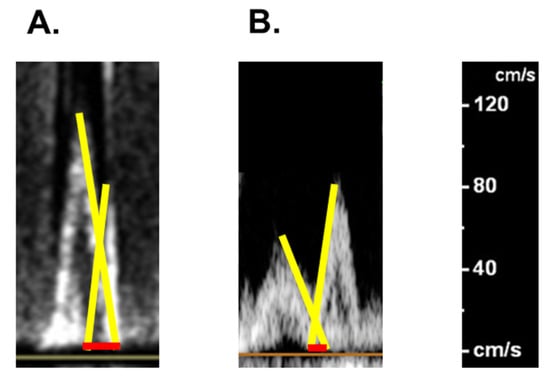

2.2. On Admission

2.3. In-Hospital Course